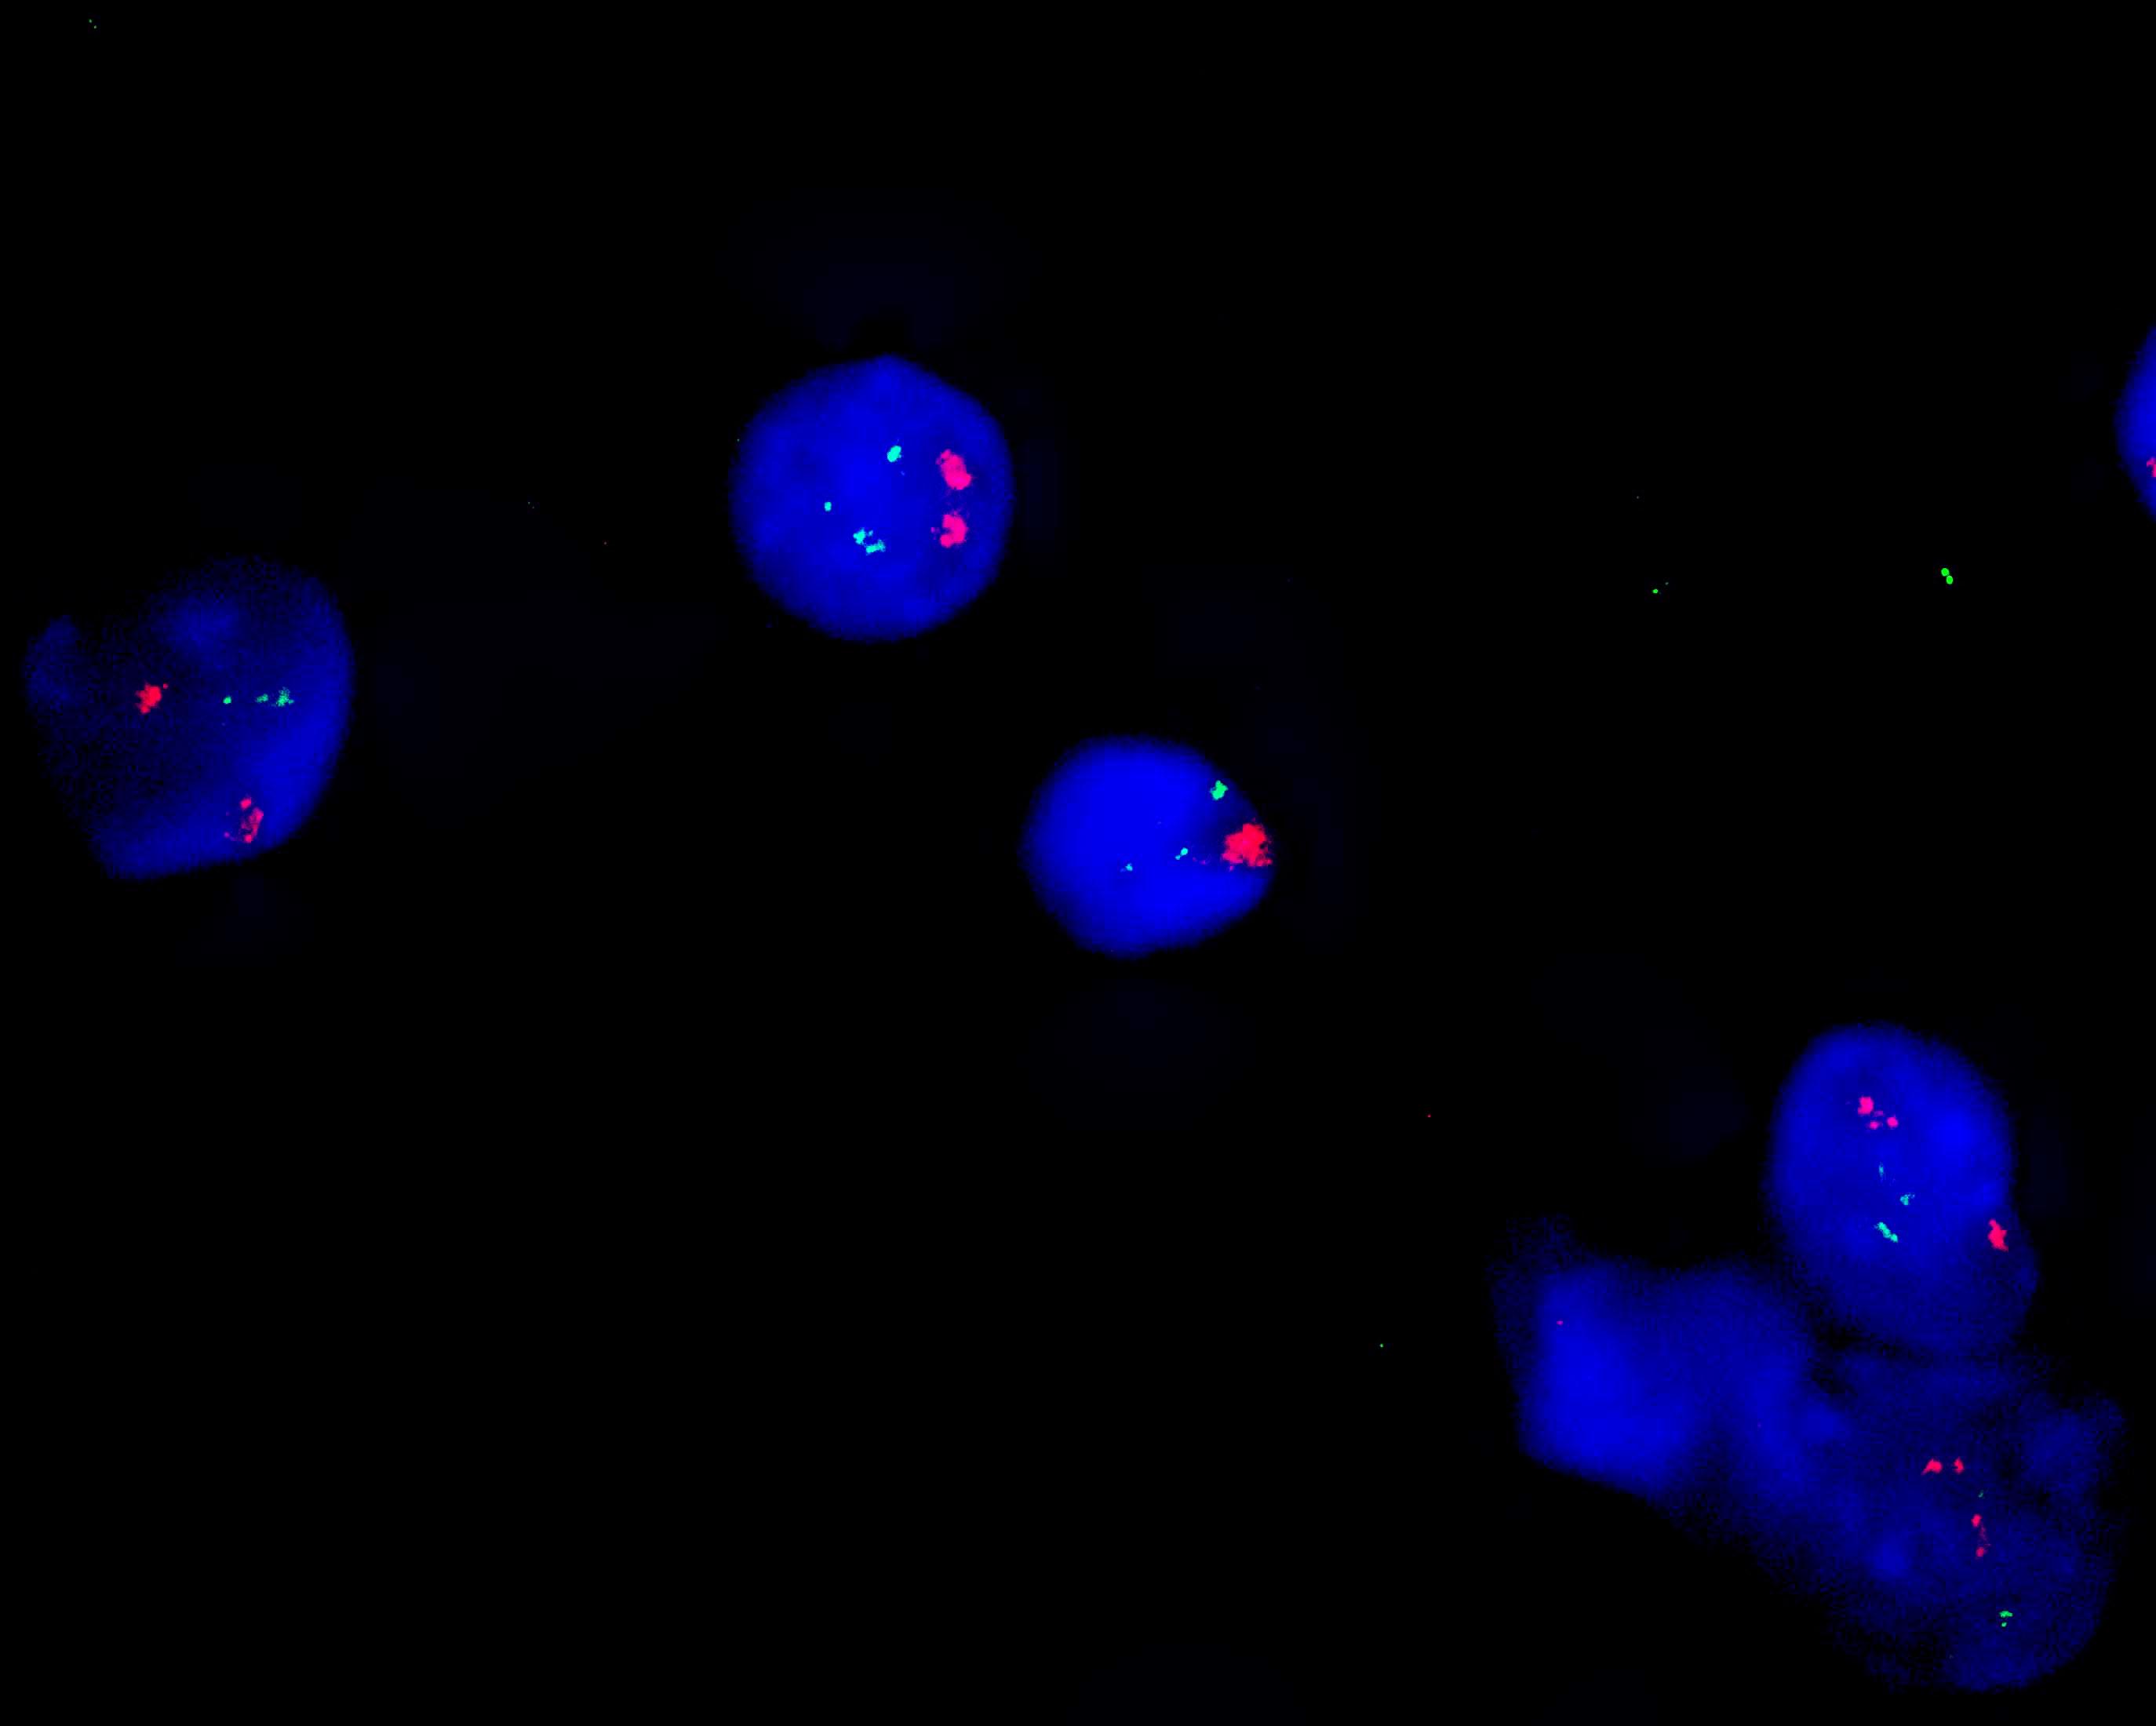

MAFB/IGH dual color probe

MAFB gene (20q12) labeled as orange, with a total length of 786 kb; IGH gene (14q32) labeled as green, with a length of 1580 kb.